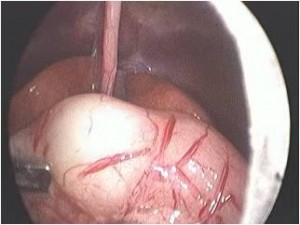

Torsion of Left Undescended Testis (Pre operative and Operative Photo)